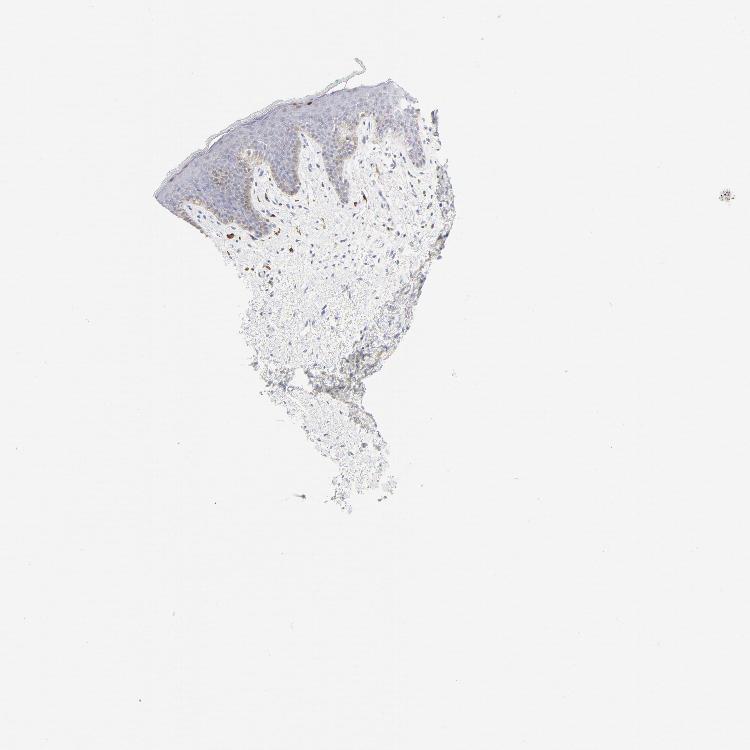

SKIN 1 - Antibody stainingi

Antibody staining in the annotated cell types in the current human tissue is reported as not detected, low, medium, or high, based on conventional immunohistochemistry profiling in selected tissues. This score is based on the combination of the staining intensity and fraction of stained cells.

Each image is clickable and will lead to virtual microscopy that enables deeper exploration of all samples and also displays staining intensity scores, fraction scores and subcellular localization as well as patient and tissue information for each sample.

Antibody HPA003316Antibody HPA003479

Keratinocytes Medium-